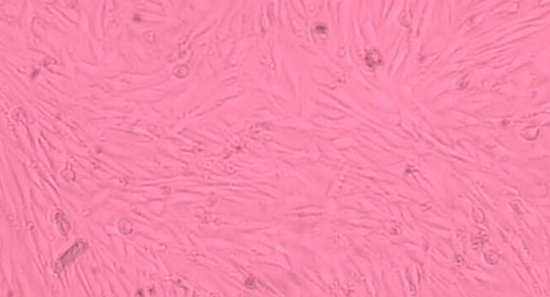

贴壁;上皮细胞样

组织来源:食道

培养条件:1640 +10% FBS

形 态:贴壁;上皮细胞样

| HZ-H601 | KYSE70;人食道鳞状细胞癌 | 1×10^6 cells/瓶 | 询价 | 下载 |